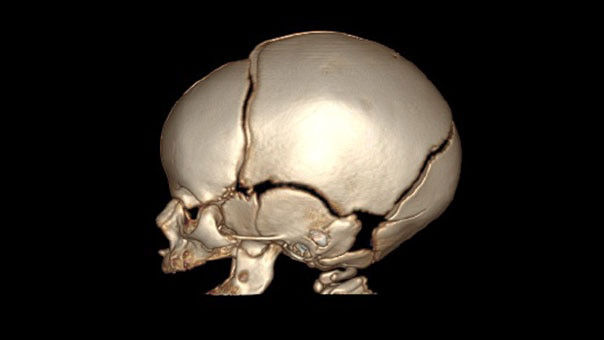

Revolution™ CT with Apex Edition upgrade

Explore our versatile CT platform with built-in scalability and upgradability. Choose the cost-effective hardware and powerful software configuration you need now and easily integrate advanced capabilities in the future